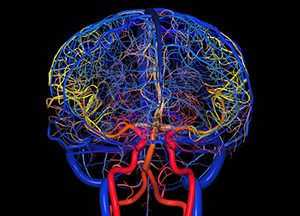

Общие сведения о базальном кровообращении, его сосудистой структуре и её функциях

Виллизиев круг является самым началом всей кровеносной сети, поднимающейся от основания головного мозга вверх как по его поверхности, так и в недрах, чтобы далее, бесконечно ветвясь, достигнуть каждой отдельной клетки в его тканях и структурах.

О строении этой части кровеносной системы

Существует множество вариантов построения артериального кольца основания мозга, но обязательными его компонентами являются артерии:

- передняя мозговая (её начальный фрагмент);

- задняя мозговая (на её начальном отрезке);

- соединительные (передняя и задние);

- внутренняя сонная (надклиновидный её фрагмент).

Основными сосудистыми магистралями являются 2 сонных и 2 позвоночных артерии (по одной с каждой стороны тела). Сонные входят в полость черепа посредством сонного канала, проходящего в пирамиде височной кости и открывающегося на её верхушке, позвоночные - миновав большое затылочное отверстие.

Кровоснабжение создается промежуточными «мостиками», имеющими индивидуальные особенности: они могут напрочь отсутствовать, находиться в состоянии аплазии, гипоплазии либо быть утроенными (наличие трёх элементов вместо двух, или феномен трифуркации).

В классически-симметричном варианте позвоночные артерии, сливаясь, образуют одну мощную базилярную (основную), проходящую вдоль варолиева моста и дающую ветви для питания мозжечка и продолговатого мозга. Кпереди она разделяется на 2 задних соединительных (правую и левую), на этом же уровне создавая также 2 задних мозговых.

На уровне её впадения во внутреннюю сонную с обеих сторон от анастомоза в дистальном направлении ответвляются центральные мозговые артерии (левая и правая). Ответвления обеих внутренних сонных смыкаются впереди, образуя полукружие, от которого вперёд отходят 2 параллельно пролегающих передних мозговых артерии. Соединяющая же их сзади одиночная передняя соединительная перемычка является частью дуги, образованной слиянием ответвлений внутренних сонных артерий.